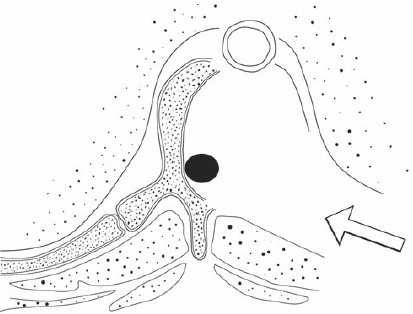

Cancer of the Spine

Cancer of the spine, both secondary and primary, are of particular interest to this practice. Dr Mobbs has undertaken further training in complex spine cancer surgery and reconstruction.

Click on the thumbnails for enlarged view